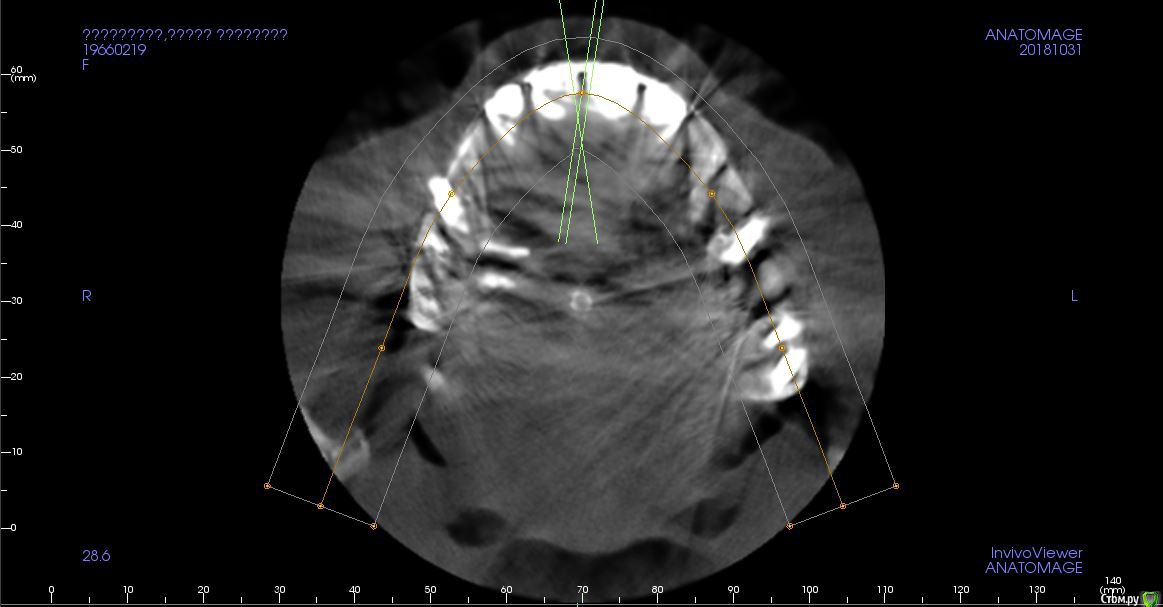

Мне 52 года, не курю. Сейчас имеет подвижность и "на честном слове" держится единая конструкция на передних  верхних. Около 27  в сторону 8 периодически образуется гнойный свищ (была литая вкладка, ее прошел врач, заложил лекарство полгода назад, гной прорывается реже).

14 имеет неощутимую мной подвижность (хирург сказал). 35-имплант, был в паре под единой коронкой с 36 (оба 2006 года). 3 мес. назад 36 дезинтегрировался, коронку распилили, не беспокоит. 43.43 имеют наружные прикорневые пломбы. 46-имплант 2009 года, конструкция на месте очень длительно отсутствующего зуба, специально задумана под углом и открыта для ежедневного ухода, тоже не беспокоит. Зубной ряд был идеально полностью восстановлен в 2010 году. После были удаления 18, 28, 47.   Заранее благодарна за все профессиональные советы.